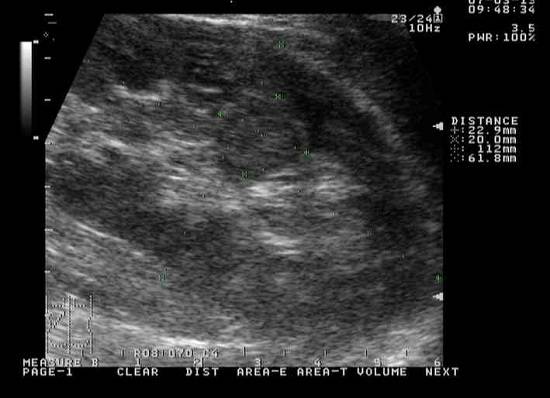

Выявить кистозные образования можно только при специфических исследованиях. К ним относят ультразвуковое исследование, магниторезонансная томография, компьютерная томография и урография.

При ультразвуковом исследовании можно выявить кистозные образования 3 и более мм. Методами томографии выявляются кисты 1 и более миллиметра. Урография хороша только при синусных кистах, так как скопление контраста имеет диагностическое значение только для исследования мочевыводящих путей.

Самым распространенным диагностическим методом исследования, при помощи которого диагностируют почечные проблемы, в том числе определяют, что уже подверглась негативному воздействию паренхима, образовалась синусная киста правой почки или левой, является ультразвуковое исследование.

Ультразвуковая аппаратура позволяет выявить кисты синусные почек, достигшие в размере 3 или более миллиметров.

Однако УЗИ является не единственным способом диагностики. Наряду с ним существуют и другие эффективные способы инструментальной диагностики, к которым относятся компьютерная томография, МРТ, урография.

При помощи такой инструментальной диагностики удается оценить работоспособность почек, установить наличие патологий, степень поражения органа.

Крошечные кисты, размеры которых равны 1 мм, отлично диагностируются при проведении томографии.